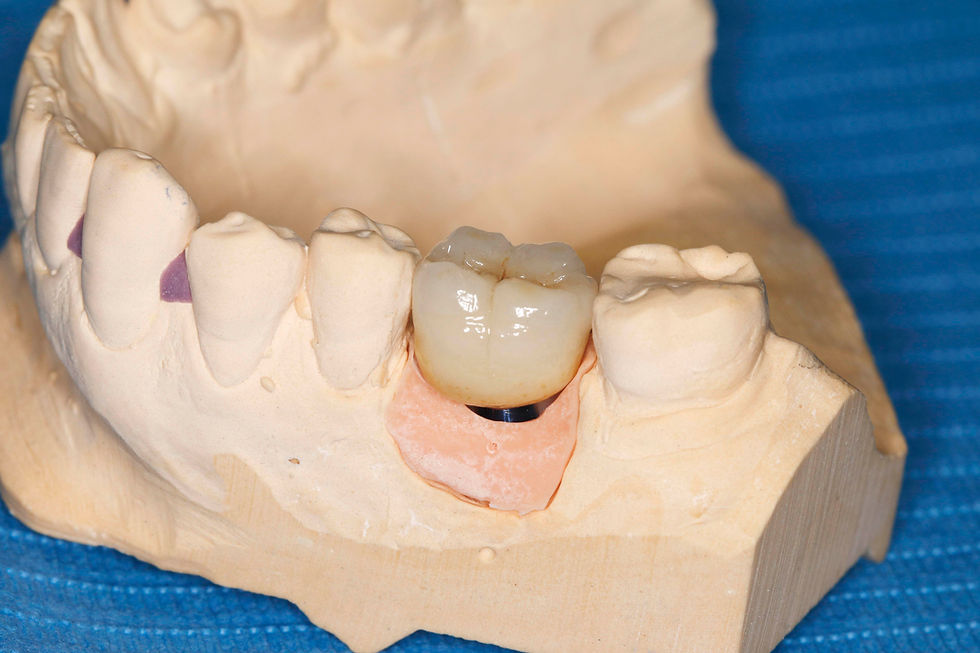

The definitive crown, made of layered zirconia, is delivered from the laboratory.